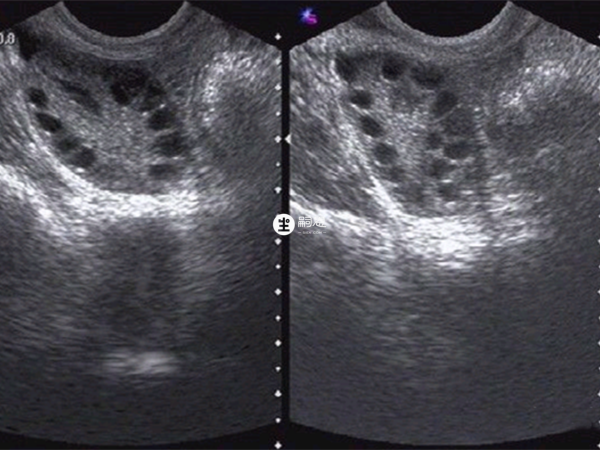

多囊卵巢綜合症是一種複雜的內分泌及代謝異常所致的疾病,其會導致女性出現慢性無排卵、高雄激素血癥,使其不孕不育。該疾病一般都需要通過促排卵質量幫助懷孕,根據臨床資料統計來看多囊卵巢懷孕機率可以達到25%左右,如果是做試管助孕,成功率能更高,可以達到50%左右。下面就為大傢俱體介紹輕微多囊卵巢綜合症做幾代試管嬰兒好成功率高: